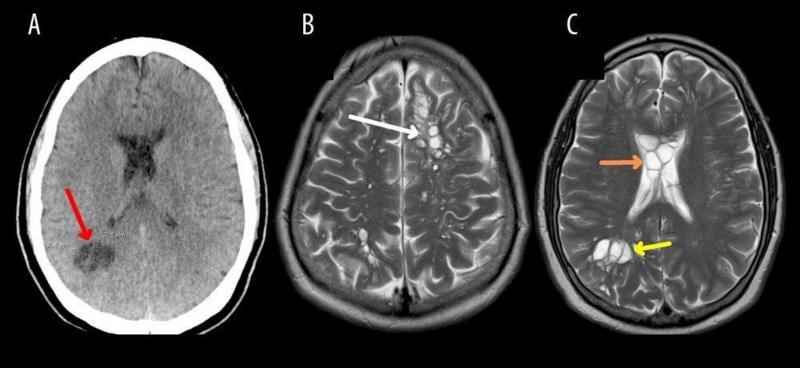

Exámenes que detectaron las larvas causantes de las migrañas. Créditos: American Journal of Case Reporters